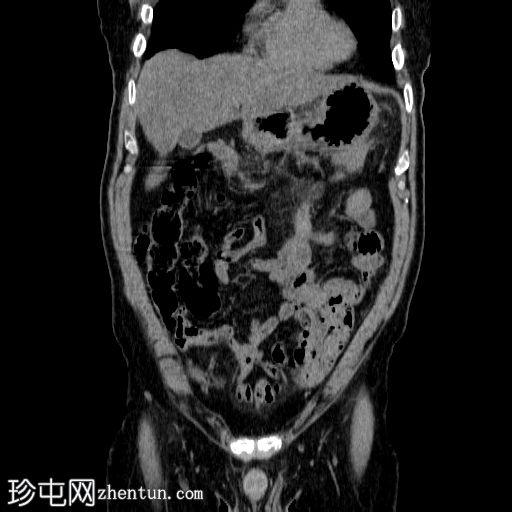

轴向

非造影

胰体尾弥漫性增大,特征为胰腺实质低强化,无明显坏死区域。

该病灶与以下表现相关:

胰周筋膜平面边界不清的污迹,无明显壁形成、气室、固体碎片或血液产物。

多个亚厘米大小、非特异性的腹主动脉旁淋巴结和肠系膜淋巴结,可能具有反应性。

病变范围如下:

病变横向延伸至左前肾旁间隙,伴有Gerota筋膜增厚。

病变向下延伸至盆腔。

无肠系膜或脾脏血管阻塞的证据。

未见导管扩张或钙化。